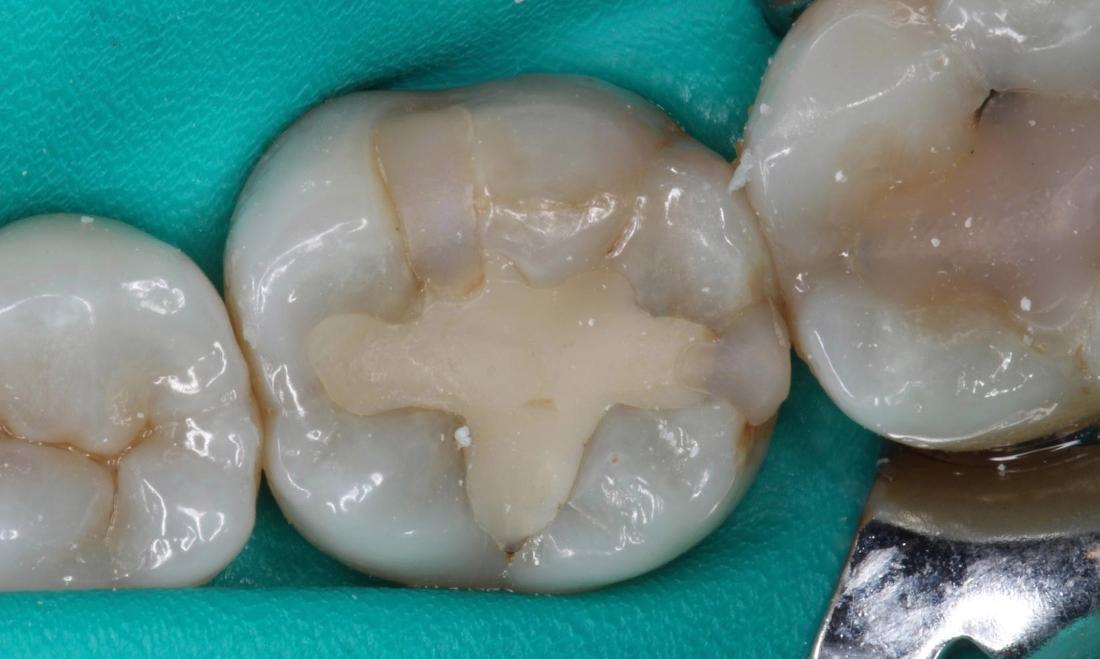

Our patient flew in from out of town to have this filling replaced. The edges of the filling were starting to leak, allowing bacteria to damage the tooth underneath the filling. A dental dam was used to isolate the teeth. We removed the old filling and replaced it with a new tooth colored filling.